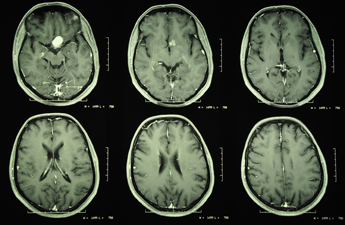

Meningiomas are benign tumours that arise from the linings of the brain (the meninges). There are no specific predisposing factors to these sorts of tumours. They can occur anywhere along the inner surface of the meninges, either within the brain cavity or within the spinal canal. The fact that they are benign means that they grow very slowly and as a result, patients will often have had these for many years before they are diagnosed with the tumour.

The symptoms that they present with are a function of both their size and site. If a meningioma is growing in a part of the brain cavity adjacent to a relatively ineloquent (non-functional) part of the brain, it can become quite large without causing symptoms.

In other more sensitive areas of the brain, meningiomas can create symptoms very early, either due to pressure on the brain or irritation of nerves exiting from the brain. As a consequence of this, there is no “typical” symptom arising from meningiomas. Due to their varied size and site, there is no single treatment solution. The neurosurgeons of the Brain and Spine Clinic would consider all of these factors including your medical history to formulate a very individualised treatment for your meningioma.